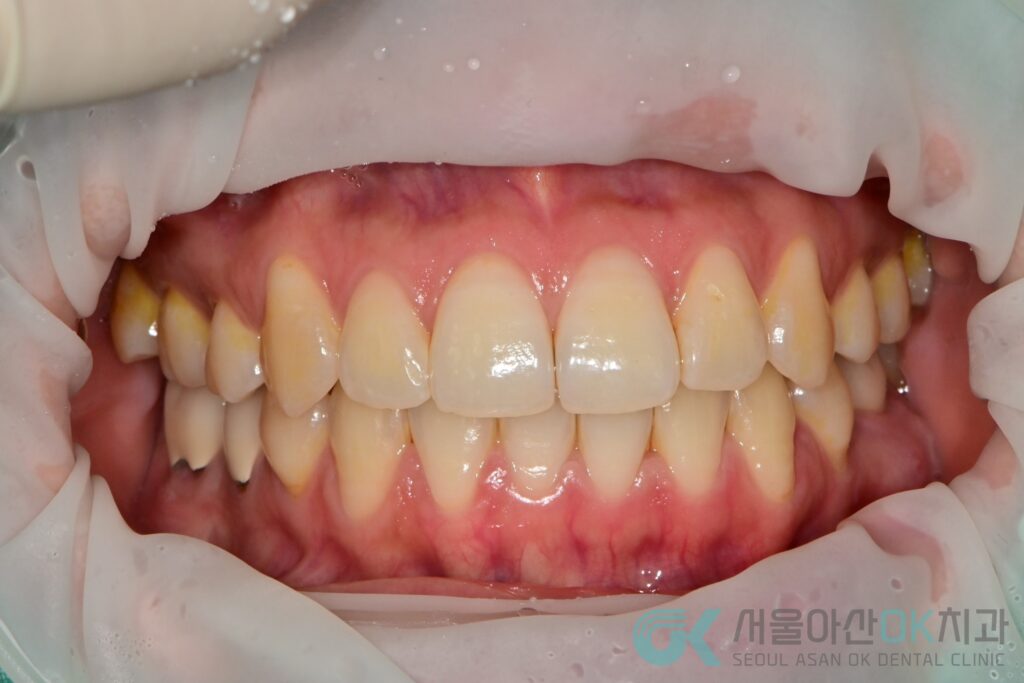

- 파노라마/구내사진 평가 중 좌하악 제1대구치(#36) 부위에서 육안상 부종이 확인

- 임상 소견 : 부종(염증성), 협측 골 소실이 진행된 상태로 기록

- 전반 상태 : 만성 복합치주염 진단 하에 스케일링 및 치주치료가 병행 진행